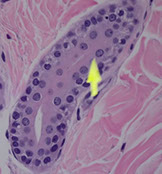

Hair follicles - connect to surface

- hair shaft is the pink thing in the middle, surrounded by epithelial layer, sebaceous glands drain into hair follicles

- dark blue cells, matricle cells or germinative epithelium, actively dividing, grows quicky, producing hair

- pink hair papilla grows into hair bulb, giving it nourishment

- hair shaft made of dead keratinocytes packed together

- inner root sheath has trichohyaline granules and looks pink

- outer root sheath, made of glycogen-filled cells that look like piano keys

- adventitia is the bright pink layer after outer root sheath

- melanocytes in the roots give hair its pigment (hair color)

Arrow to hair shaft, in a hair follicle